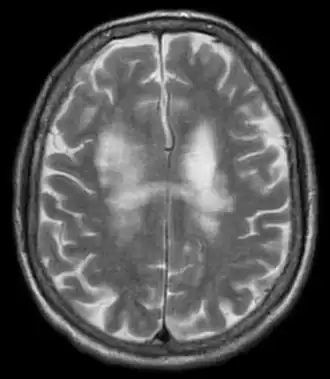

Магнитно-резонансная томография (МРТ) является по сравнению с компьютерной томографией предпочтительной методикой. В Т2-взвешенных изображениях определяются гиперинтенсивные очаги — асимметрично распределенные в белом веществе лобных и теменно-затылочных отделов, а также в корковом веществе, в стволе мозга и мозжечке, без — или с незначительным захватом контрастного вещества; увеличения объёма ткани не наблюдается. В Т1-взвешенных изображениях эти очаги гипоинтенсивны. У одной трети пациентов также обнаруживаются инфратенториальные очаги, которые могут также определяться изолированно.[11].